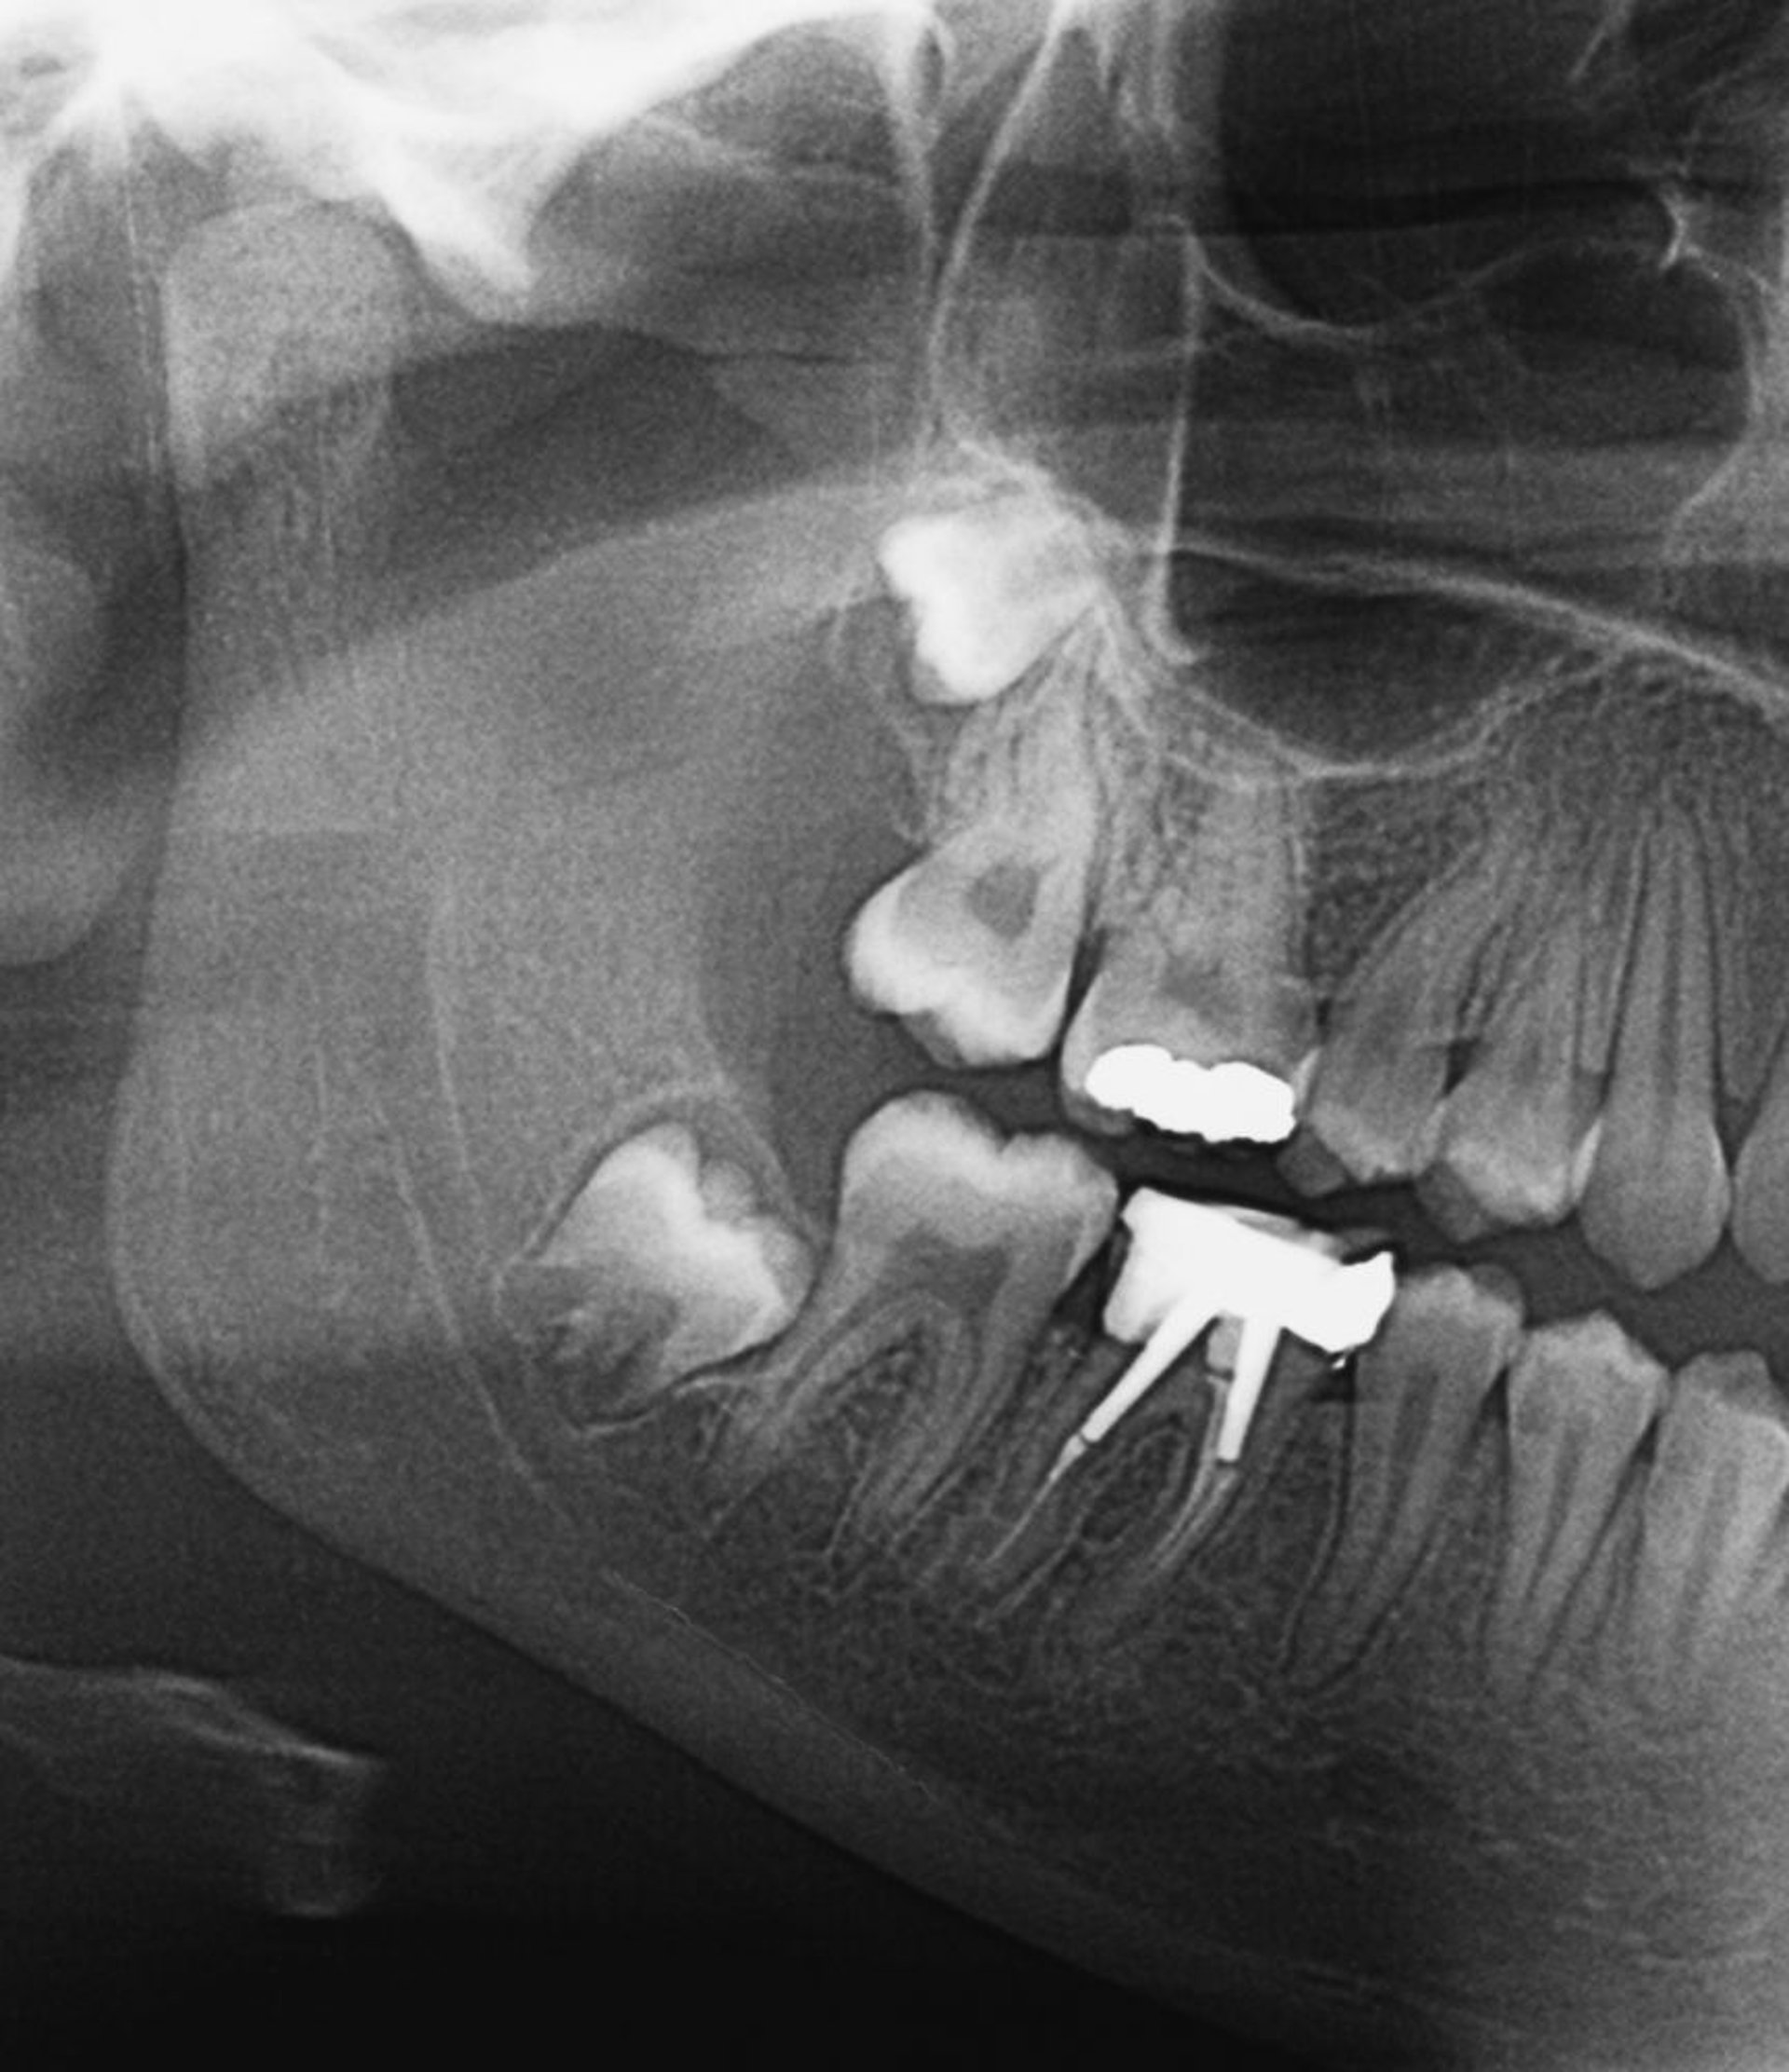

Muelas del juicio impactadas

Esta radiografía muestra las muelas del juicio impactadas. Cuando las muelas del juicio entran en erupción, o si están parcialmente impactadas, puede desarrollarse una pericoronitis.

ZEPHYR/SCIENCE PHOTO LIBRARY